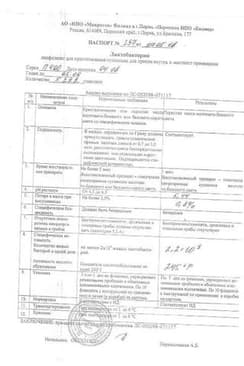

Лактобактерин лиофилизат для приготовления суспензии для приема внутрь и местного применения ампула 5доз 10 шт

Сертификаты